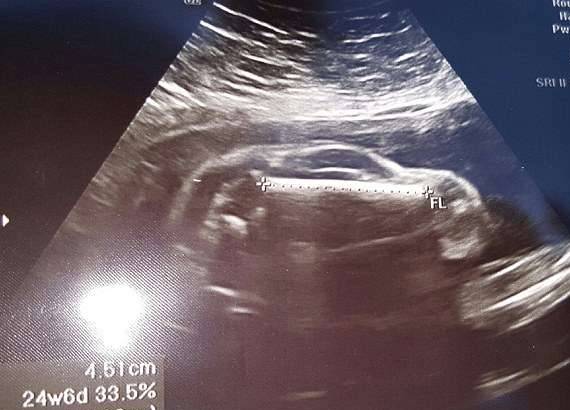

第一次看到宝宝的超音波照片,準父母们一定会很激动。但不久前,国外一名网友带妻子去做检查时,却看到了惊人的一幕。超音波检查照片中显示的不是胎儿的形状,反而看起来像一台跑车。他觉得非常吃惊,将这张照片上传到网路上与大家分享,很快就有490多人留言回应。

▼这张超声波照片看起来很像跑车,就连车窗、车轮都看得很清楚。

▼还有人说「不要忘了踩煞车」。